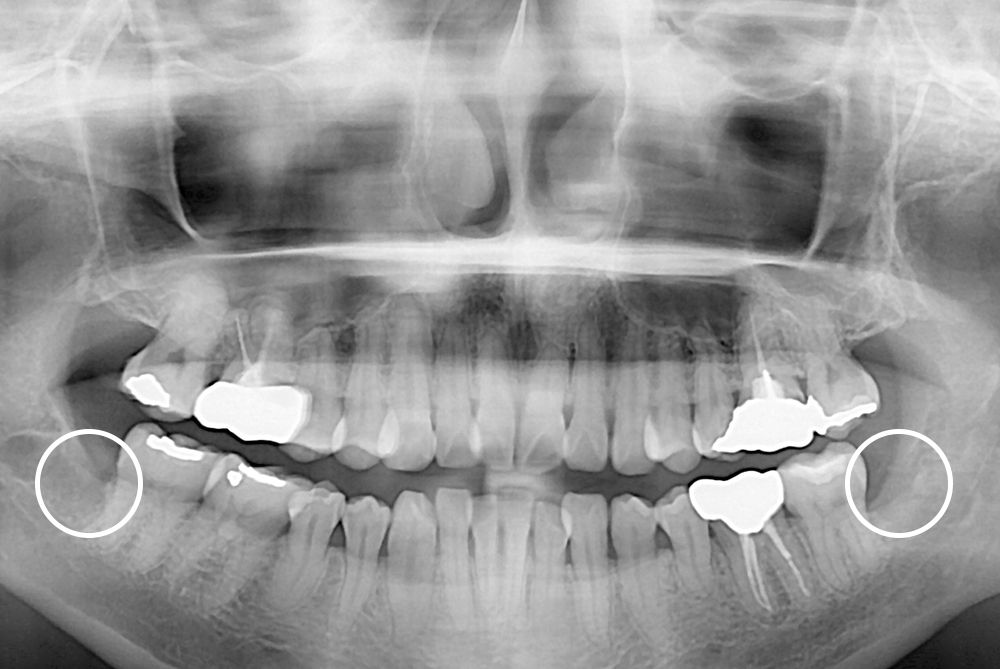

[사랑니] 매복 사랑니 발치

치료후 : 2017-08-29

세종치과는 구강악안면외과학 박사이신 원장님이 발치하는 치과입니다.